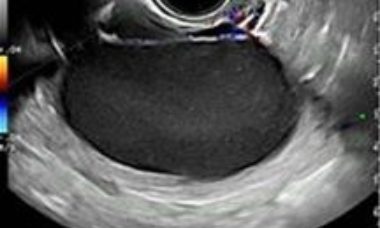

VISUOG is our Visual Encyclopedia and aims to provide medical professionals with up-to-date information on the clinical use of ultrasound in obstetrics and gynecology.

The rigorous peer-review process overseen by experts ensures that the VISUOG educational materials are accurate, evidence based, and aligned with the latest advancements in the field.